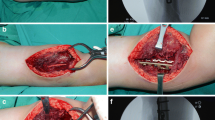

All specimens survived the cyclic loading phase and underwent the load-to-failure tests. In the LCP group, in 10 out of 12 specimens the mode of failure was a diaphyseal shaft fracture at the distal plate peak (Fig. 6b), whereas in the other group the proximal screws were pulled out of the plate (Fig. 6a). The load at failure revealed no significant differences (p = 0.65) for the low-profile double plates (1560.83 N 148.05 N) and the LCP (1615.83 N 384.32 N) (Fig. 7).

Mode of failure. The mode of failure under maximum loading of the specimens is shown. The double plates failed with a proximal screw pull-out of the plate (a), whereas in the LCP group, in ten out of twelve specimens the mode of failure was a diaphyseal shaft fracture at the distal plate peak (b). In the double-plate group, none failed by a shaft fracture